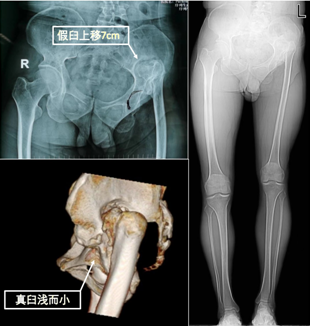

成人发育性髋关节脱位是严重的致残性疾病,常导致跛行、髋关节疼痛及功能障碍,从而丧失劳动能力,手术治疗是极为有效的治疗方法。但是由于患者自幼出现解剖结构异常,情况复杂,尤其对于高位发育性髋关节脱位,手术极具挑战性。患者46岁,因跛行40余年,左髋疼痛5年入院。患者入院后进行了全面的评估,检查发现左下肢较对侧短缩7cm,以至于脊柱及骨盆严重倾斜,影像学检查提示患者左下肢骨骼发育异常,髋臼浅而小,股骨头脱位上移远离真臼位置并坏死变形,股骨颈干角及前倾角明显异常。

术前影像资料